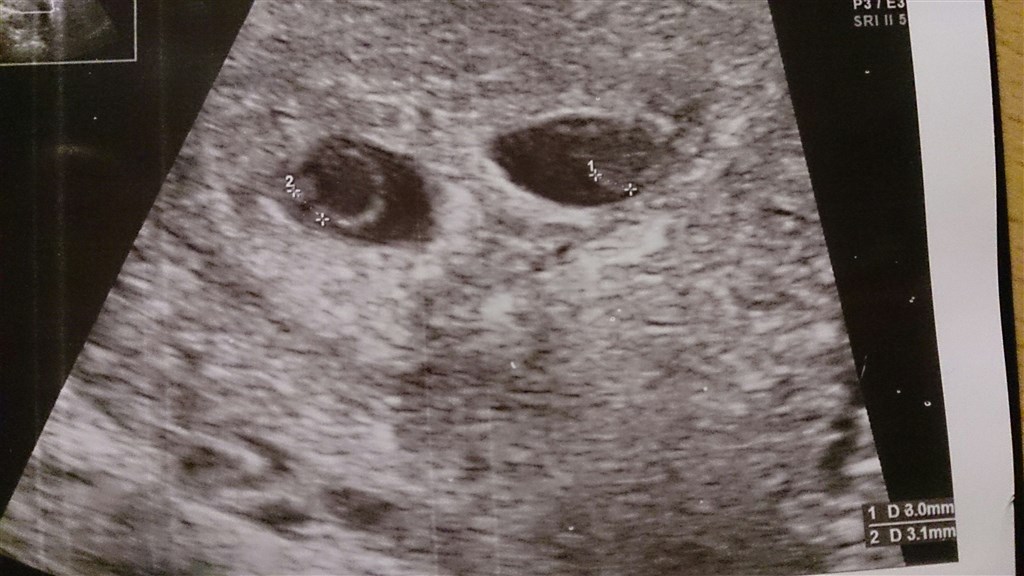

Hun scannede uden på maven. To stks sagde hun.

De var 3 mm begge to.

Hun ku ikke se hjerteblink endnu, men vi ku se noget meget småt.

Men man kan ikke så hjerte blink i uge 4/5.

Og hun mente det så ud som det skulle.